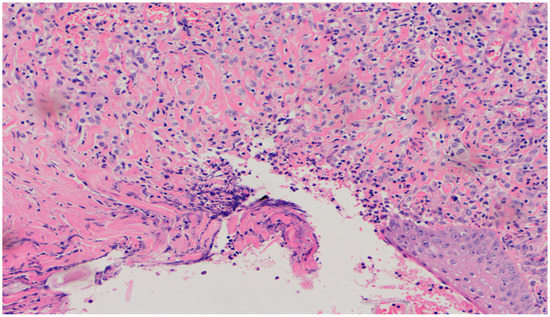

On day 20, the histopathological appearance varied significantly. In wound D1 treated with the 1% propolis ointment, the intensity and nature of the inflammation regressed. A small inflammatory lymphocytic infiltration was found. An increase in epidermization was also noted, from being slight on day 15 to high on day 20. Additionally, the wound was slightly neovascularized.

The wound from the experimental group D2, treated with the 1% propolis ointment, showed a regression of inflammation. The wound began to show a slight epidermization only on day 20. There was also a decrease in neovascularization, from high on day 15 to low on day 20, and no superficial necrosis was found. Wound D3, treated with a mixture of 1% propolis and 1% nanosilver, showed no changes on day 20 in the intensity and type of the inflammatory infiltration. Just like the wound in group D2, it was characterized by a slight epidermization only on day 20, with the simultaneous development of superficial necrosis, from being slight on day 15 to large on day 20. The wound was highly neovascularized. In the wound from the control group K, treated with sulfathiazole, the intensity and type of the inflammatory infiltration did not change on day 20, and additionally, epidermization was inhibited. The histopathological findings from day 20 are presented in Table 11 and Figure 20 and Figure 21.

Figure 20. Mixed lymphocytic-granulocytic inflammatory infiltration, medium density, in the dermis (100×, H-E) in the wound treated with sulfathiazole on day 20.

Figure 21. Focal, detachable necrosis on the epidermal skin lesion. Under the epithelium, a low-density lymphocytic inflammatory infiltration (40×, H-E) in the wound treated with the 1% propolis ointment on day 20 is visible.